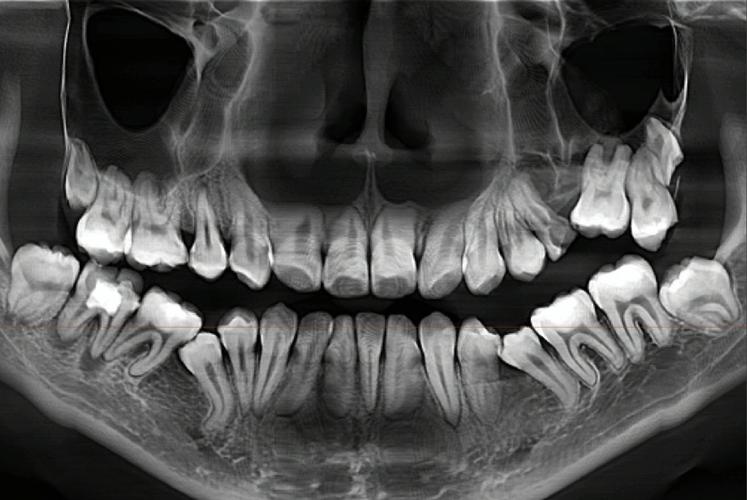

通过全景片(曲面断层片),可清晰观察全口牙齿的数量、形态及位置,包括是否存在“多生牙”(额外牙齿)、“缺失牙”(先天性或后天性缺失)、“埋伏牙”(未萌出的牙齿,如阻生智齿)等异常,若存在埋伏牙,需判断其位置、方向是否会影响矫正中牙齿的正常移动,或是否需要提前手术拔除;若存在多生牙,可能占据正常牙齿的生长空间,导致牙列拥挤,需在矫正前处理,还能观察牙根形态是否正常(如弯曲、短根),牙根周围是否有吸收或病变,这些因素直接影响牙齿移动的稳定性和安全性。

评估牙槽骨健康状况:牙齿移动的“土壤”

牙齿能否在牙槽骨中稳定移动,取决于牙槽骨的厚度、高度及密度,通过全景片和CBCT(锥形束CT),可测量牙槽骨的骨量是否充足,若牙槽骨过薄或存在吸收(如牙周病患者),牙齿移动过程中可能发生骨裂或松动,需先进行牙周治疗,调整移动力度和速度;若牙槽骨条件不佳,甚至可能需要植骨来为牙齿移动创造“安全土壤”。

颞下颌关节(TMJ)是连接下颌骨与颅骨的关节,负责张口、闭口等动作,若关节存在结构异常(如关节盘移位、骨赘),可能引发疼痛、弹响甚至张口受限,通过关节片或CBCT可观察关节形态,判断是否需要在矫正中调整咬合关系,避免加重关节负担,全景片还能发现颌骨内的囊肿、肿瘤等病变,防止在矫正过程中刺激病变进展。